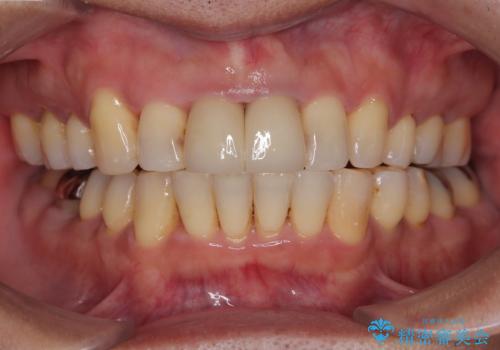

ホワイトニングを併用し、治療前と比べて自然でとても明るい口元となりました。